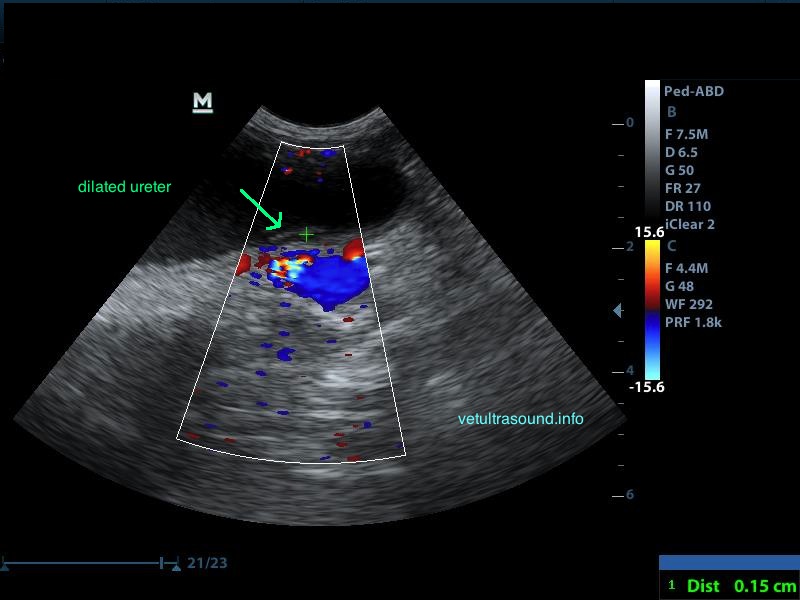

Ευρήματα: Στον υπέρηχο κοιλίας βρέθηκε επώδυνη διόγκωση και των δύο νεφρών με πάχυνση της φλοιώδους ουσίας, η οποία παρουσίαζε έντονη ανομοιογένεια. Οι νεφρικές πύελοι ήταν ήπια διατεταμένοι και στο εσωτερικό τους παρατηρήθηκε αφθονία ιζήματος. Οι ουρητήρες, οι οποίοι ήταν επίσης διατεταμένοι, απεικονίζονταν μέχρι την είσοδό τους στην ουροδόχο κύστη. Αφθονία ιζήματος βρέθηκε στην ουροδόχο κύστη. Η εικόνα αυτή είναι συμβατή με διάμεση νεφρίτιδα και στην συγκεκριμένη περίπτωση με πυοκοκκιωματώδη φλεγμονή των νεφρών, συνεκτιμώντας τα εργαστηριακά ευρήματα, τον έντονο πόνο και τη διάταση των ουρητήρων. Το resistive index ( δείκτης αγγειακής αντίστασης) βρέθηκε αυξημένο (0.77) σε μεσολόβιο αρτηρίδιο του νεφρού. Φυσιολογικά θα έπρεπε να είναι (0.6±0.06). Αυτό δείχνει πως το οίδημα του νεφρικού παρεγχύματος εξαιτίας φλεγμονής ή οποιαδήποτε άλλης διήθησης, νεοπλασματικής ή μη, πιέζει τα αγγεία και αυξάνει την αντίσταση του αίματος προς το νεφρό. Ένα επιπλέον διαγνωστικό βήμα για την διερεύνηση της αιτίας, για την αποτελεσματικότερη θεραπεία και την εγκυρότερη πρόγνωση, είναι η λήψη κυτταρολογικού υλικού από το νεφρικό παρέγχυμα και ούρου από τη νεφρική πύελο για καλλιέργεια, στα οποία ο ιδιοκτήτης δεν θέλησε να προχωρήσει.